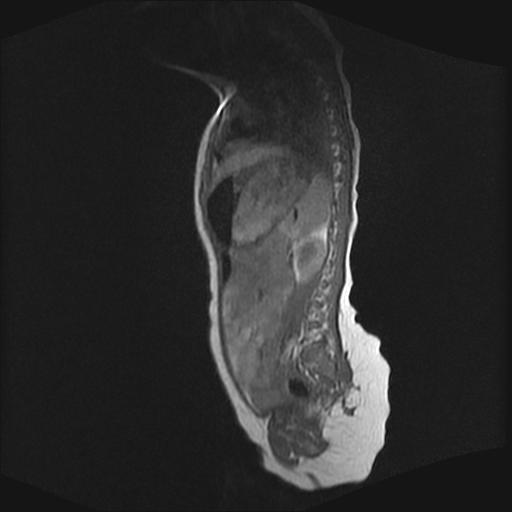

四个月的女婴,ct示脊膜膨出.

脂肪脊髓脊膜膨出

脊柱裂、脊膜膨出